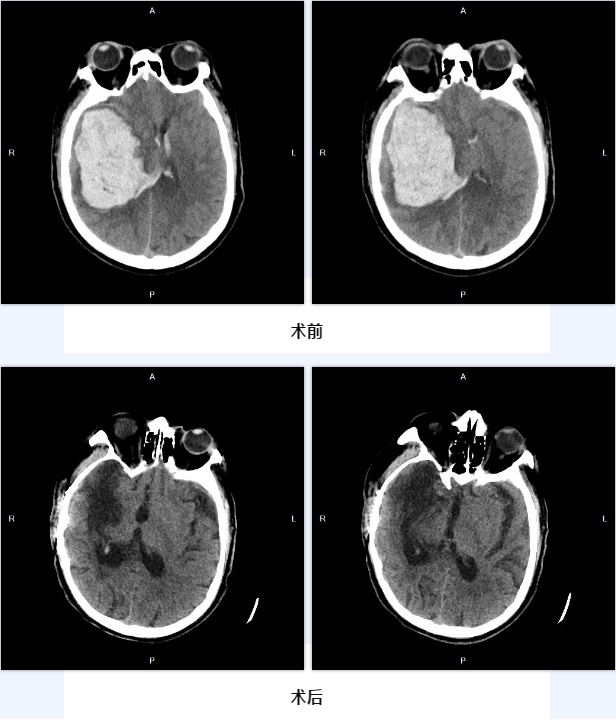

今年3月20日,65岁的陈大伯突发意识不清,呼其不应,并伴有呕吐症状,家人赶紧将其送往北京燕化医院急诊科,经问诊,老人患有高血压十余年,近期未规律服药,考虑高血压脑出血可能大;经头颅CT检查显示,患者右侧基底节区脑出血破入脑室,量较大,约100毫升,中线明显移位,右侧瞳孔已散大、固定,直径4.5mm,光反射消失,呼吸微弱,心律不齐,脑疝形成,病情危重、凶险,需要马上进行手术。

以程扬主任为首的神经外科团队根据影像检查,在认真分析了患者的病情后,经过综合评估,决定立即为患者施行开颅去骨瓣减压手术,对颅内血肿进行清除。

在认真和家属沟通了手术风险及并发症并经家属同意后,经过充分的术前准备,在手术室、麻醉科的密切配合下,程扬主任成功在显微镜联合内镜技术下为患者实施了开颅颅内血肿清除、去骨瓣减压术,历时约2.5个小时,手术顺利结束,且非常成功,血肿清除理想,术后患者原本散大的瞳孔已经缩小,转入ICU进一步对症诊疗。